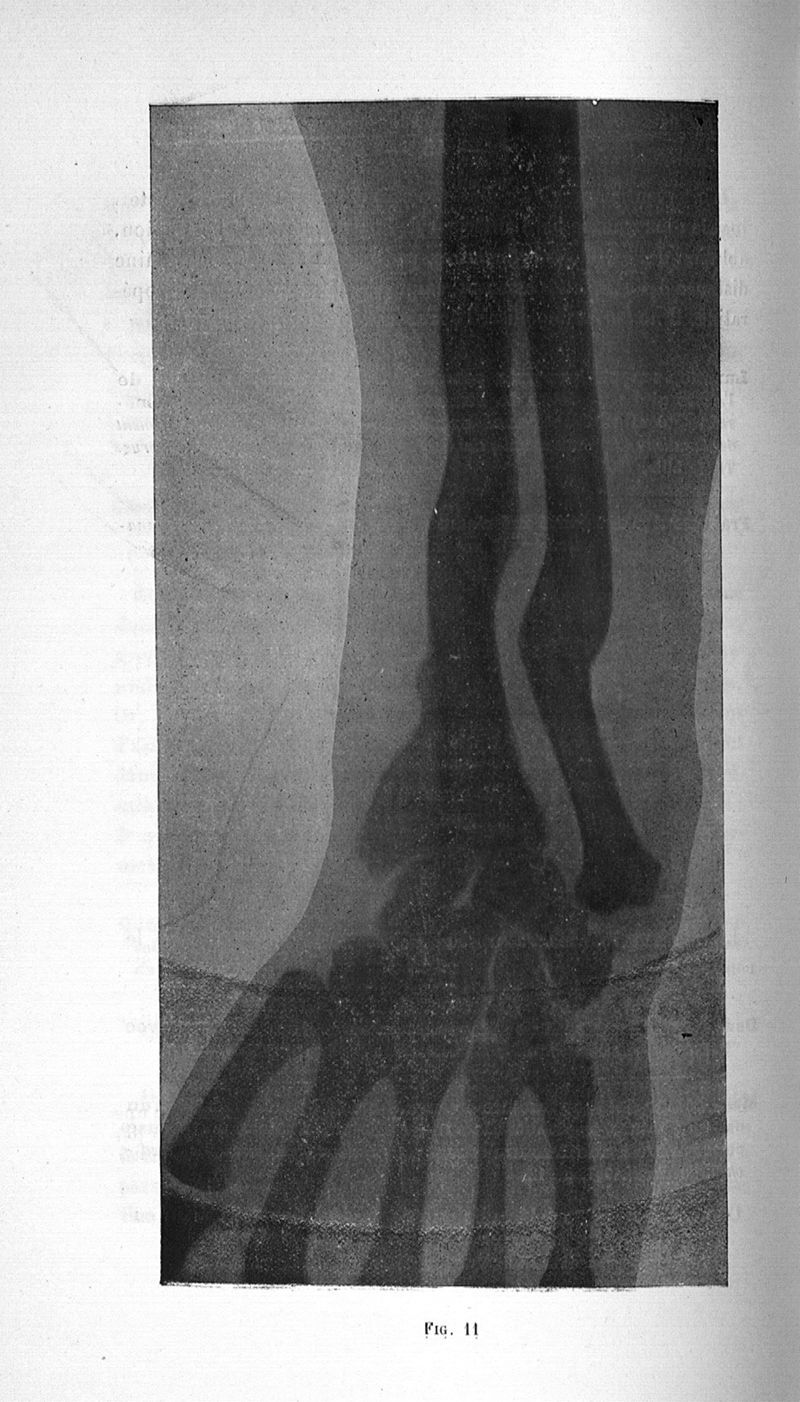

Vanverts, Julien Louis Joseph.

Titres et travaux

Paris, G. Steinheil, 1907.